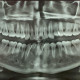

Alo Dokter. Pasien pria berusia 26 tahun datang ke klinik dengan keluhan nyeri di area gigi geraham bawah kanan yang sudah berlangsung selama satu minggu. Pasien menyatakan nyeri terasa berdenyut, terutama saat mengunyah dan saat mengonsumsi makanan panas atau dingin. Pasien membawa hasil rontgen dibawah. Apakah perlu dilakukan tindakan atau cukup dengan obat-obatan saja? Mohon advice, dok, terutama TS dokter gigi 🙏🏼